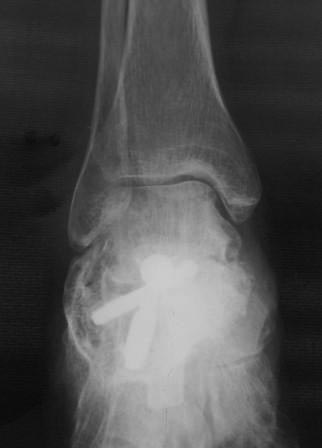

[Ortho] Постравматическая деформация пяточной кости

Уважаемые коллеги.Операция была произведена 22.01.16г. только

сегодня имеется возможность отправить. L-образный доступ. . при ревизии

подтаранный сустав сохранен, поэтому линейная остеотомия, подкожная

ахиллотомия. . подготовка ложа, и смещенный отломок спущен вниз к ложу,

но  до конца не смогли. фиксирован двумя винтами. по медиальной

поверхности рубец плотно спаянный с костной осколькой пока не трогали

из-за опасения инфицирования, после заживления раны потом будем думать

что делать.